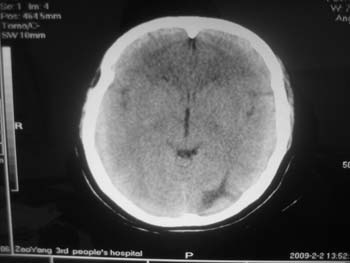

女。44岁,语言障碍三天,右侧上肢时而麻木。时而好转。其它图像未见异常。图像有点差请大家见谅。mg]/upload/forum/2009/02/0214453656449.jpg[/img]

双侧额叶密度低,考虑线束老化或脑梗塞?

左侧枕叶脑软化灶?

双侧额叶脑梗塞,左侧枕叶脑软化灶,